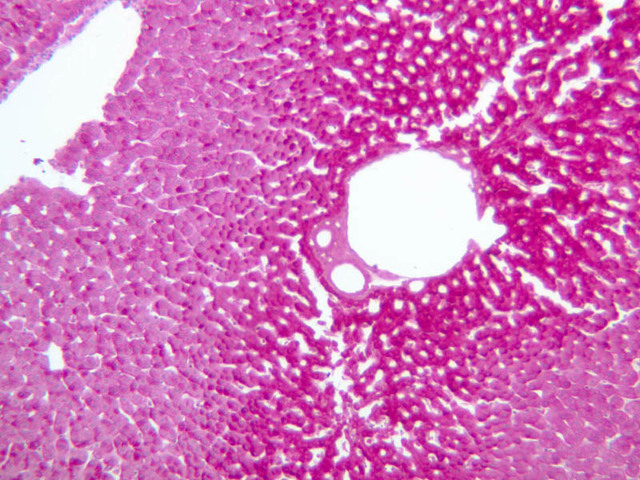

Examine the H&E-stained sections of liver (slides B-29 [10x, 20x, 40x-labeled] [2.5x-labeled, 10x, 20x, 40x] [10x-labeled, 20x, 40x-labeled] and B-30 [2.5x, 10x-labeled, 20x]). At low power, identify the connective tissue capsule (Glisson’s capsule), central veins and portal triads (portal canals). Note that the cells of the liver parenchyma (hepatocytes) appear as cords--more accurately, plates--of cells that radiate out from the central veins and partially enclose blood spaces known as hepatic sinusoids. Note that the plates of hepatocytes appear to branch and fuse and that, as a rule, they are only one or two cells thick. Do you see any binucleate hepatocytes?

Using the 10X (B-29, B-30)and 40X (B-29) objectives, examine several portal triads, noting the variable number of profiles of hepatic artery, portal vein and bile duct that comprise the portal triad. Near the boundary between adjacent lobules, try to find some of the small elements of the bile duct system known as canals of Hering.

(1) Identify the portal triads that define the boundaries of a “classic” liver lobule (B-29). Since it surrounds a central vein, the classic lobule may be thought of as emphasizing the endocrine functions of the liver.

(3) A liver acinus is roughly elliptical in section. Its shorter axis (equator) is defined by the terminal branches of the hepatic artery and portal vein, which course along the boundary between adjacent classic lobules; its longer axis is defined by the two central veins nearest the equator (B-29). Although it is more difficult to visualize a liver acinus than a classic or portal lobule, the concept of acinar organization is very useful because certain features of liver metabolism best fit the acinar model.